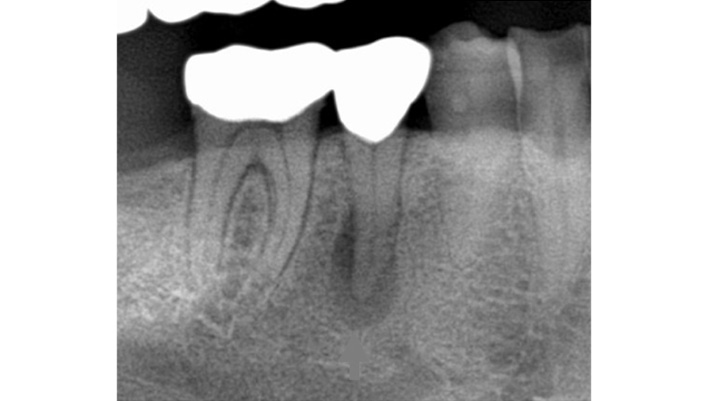

治療前

患者様は「他院で神経を取るしかないと言われたが、できれば神経を残したい」とのご希望で来院されました。初診時には冷たいものがしみる症状はありましたが、自発痛や打診痛はなく、診査の結果、歯髄を温存できる可能性があると判断しました。

治療では拡大視野下でむし歯の感染部分を正確に除去し、MTAを用いた歯髄温存療法を実施しました。

| 主訴 | 歯に穴が空いた |

|---|---|

| 治療期間 | 1ヶ月 |

| 治療費 | ¥33,000 |

| 治療内容 | むし歯が大きく、神経を残す治療(歯髄温存療法)を行い、神経を残しダイレクトボンディングにて修復しました。 |

| 治療のリスク | 治療後に痛みが出ることがあります。また、痛みが強くでる場合は神経を取る治療に移行することもあります。 |